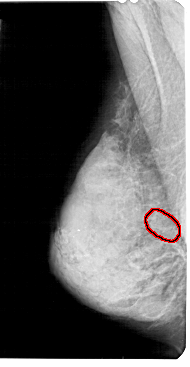

A_1936_1.LEFT_CC

LEFT_CC LINES 5146 PIXELS_PER_LINE 2911 BITS_PER_PIXEL 12 RESOLUTION 43.5 OVERLAY

FILE: A_1936_1.LEFT_CC.OVERLAY

TOTAL_ABNORMALITIES 1

ABNORMALITY 1

LESION_TYPE CALCIFICATION TYPE AMORPHOUS DISTRIBUTION DIFFUSELY_SCATTERED

ASSESSMENT 4

SUBTLETY 1

PATHOLOGY BENIGN

TOTAL_OUTLINES 1

BOUNDARY